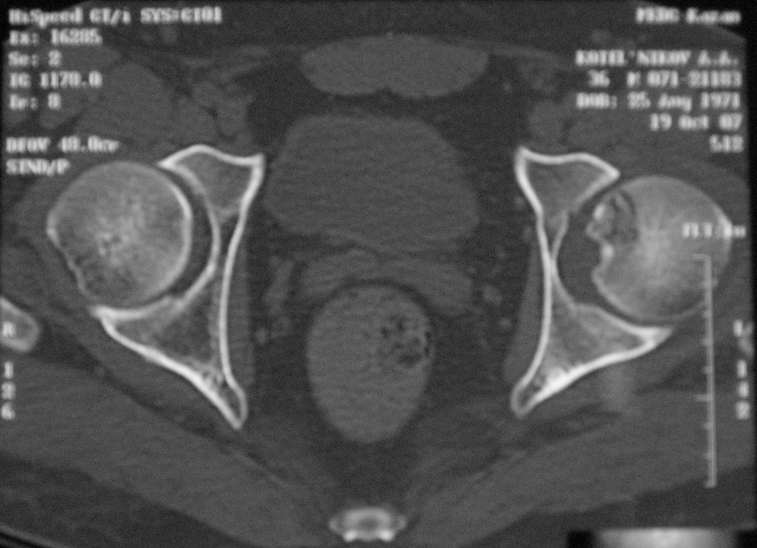

Молодой человек, 37л. Начало заболевания сентябрь 2007, резкие боли в области лев. тазобедренного сустава, повышение температуры до 39 гр., в течение недели, лабораторные данные: лейкоцитоз со сдвигом влево. Посев крови на стерильность возбудителя не выявил. По данным Рг, РКТ выставлен диагноз: Левосторонний коксит? Асептический некроз? Проводилось лечение: цефсон в/в неделю, иммобилизация кокситной повязкой 1 мес. Обратился повторно 10 дней назад с жалобами на сильные боли в левом тазобедренном суставе, белая кровь – нормограмма, СОЭ 46 мм/ч. На сегодняшний день: болей не отмечает. Лаб.данные: белая кровь – нормограмма, СОЭ 30 мм/ч. Рентген и РКТ прилагаем.

Мне представляется, что предоставлен случай аваскулярного некроза головки бедра. Для определения тактики лечения необходимо выполнить ренгенограммы лучшего качества и посмотреть все срезы на уровне головки. Предоставленные срезы -уровень ямки,т.е. малонагружаемой зоне, наличие в этой зоне участков сегментарного некроза скорее всего не приведет к деформации головки, при таком варианте разгрузка конечности на 3-4 мес может привести к благоприятному исходу.

При наличии участков некроза внутри головки близко к нагружаемой зоне для профилактики имперссионного прелома, вероятно, целесообразно выполнить Core Decompression (тема обсуждалась на форуме). В случае расположения участков некроза, затрагивающих суставную поверхность в нагружаемой зоне может быть целесообразным выполнение операций на проксимальном отделе бедра, ставящих целью выведение участков некроза из под нагрузки. Ну и протезирование, конечно, как вариант.